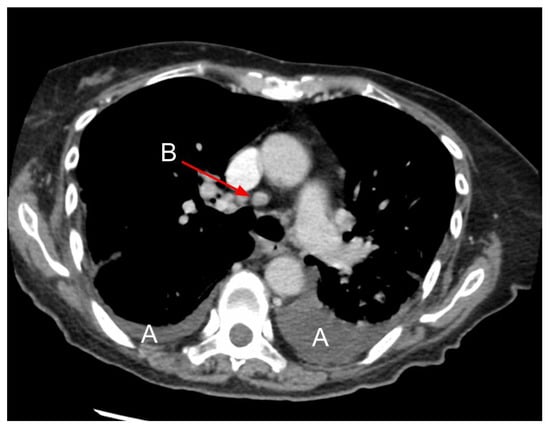

4. Chest CT

- Lewin, S.; Goldberg, L.; Dec, G.W. The Spectrum of Pulmonary Abnormalities on Computed Chest Tomographic Imaging in Patients with Advanced Heart Failure. Am. J. Cardiol. 2000, 86, 98–100. [Google Scholar] [CrossRef]

- Scillia, P.; Delcroix, M.; Lejeune, P.; Mélot, C.; Struyven, J.; Naeije, R.; Gevenois, P.A. Hydrostatic Pulmonary Edema: Evaluation with Thin-Section CT in Dogs. Radiology 1999, 211, 161–168. [Google Scholar] [CrossRef]

- Ribeiro, C.M.C.; Marchiori, E.; Rodrigues, R.; Gasparetto, E.; Souza, A.S., Jr.; Escuissato, D.; Nobre, L.F.; Zanetti, G.; de Araujo Neto, C.; Irion, K. Hydrostatic Pulmonary Edema: High-Resolution Computed Tomography Aspects. J. Bras. Pneumol. 2006, 32, 515–522. [Google Scholar] [CrossRef]

- Scillia, P.; Bankier, A.A.; Gevenois, P.A. Computed Tomography Assessment of Lung Structure and Function in Pulmonary Edema. Crit. Rev. Comput. Tomogr. 2004, 45, 293–307. [Google Scholar] [CrossRef]

- Dayem, H.A.; Gohari, A.; Endo, Y.; Shwarzberg, H.; Afari, A.; Waite, S.A. Chest Computed Tomography Features Predictive of Elevated B-Type Natriuretic Peptide Independent of Renal Function: Diagnostic Implications for Evaluation of Congestive Heart Failure. J. Comput. Assist. Tomogr. 2013, 37, 760–764. [Google Scholar] [CrossRef]

- Erly, W.K.; Borders, R.J.; Outwater, E.K.; Zaetta, J.M.; Borders, G.T. Location, Size, and Distribution of Mediastinal Lymph Node Enlargement in Chronic Congestive Heart Failure. J. Comput. Assist. Tomogr. 2003, 27, 485–489. [Google Scholar] [CrossRef]

- Chabbert, V.; Canevet, G.; Baixas, C.; Galinier, M.; Deken, V.; Duhamel, A.; Otal, P.; Joffre, F.; Remy, J.; Remy-Jardin, M. Mediastinal Lymphadenopathy in Congestive Heart Failure: A Sequential CT Evaluation with Clinical and Echocardiographic Correlations. Eur. Radiol. 2004, 14, 881–889. [Google Scholar]

- Sintou, A.; Mansfield, C.; Iacob, A.; Chowdhury, R.A.; Narodden, S.; Rothery, S.M.; Podovei, R.; Sanchez-Alonso, J.L.; Ferraro, E.; Swiatlowska, P.; et al. Mediastinal Lymphadenopathy, Class-Switched Auto-Antibodies and Myocardial Immune-Complexes During Heart Failure in Rodents and Humans. Front. Cell Dev. Biol. 2020, 8, 695. [Google Scholar] [CrossRef]